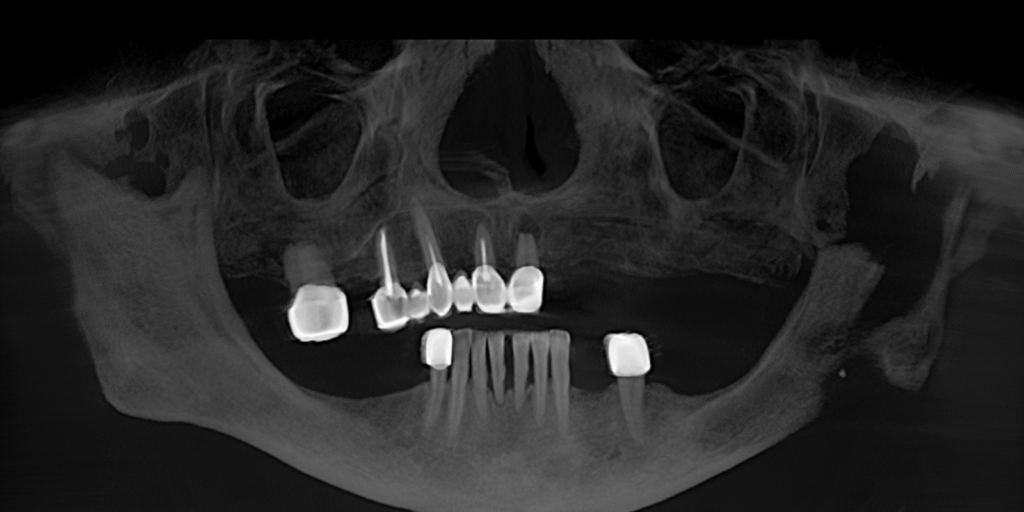

Мы провели осмотр и компьютерную томографию, чтобы оценить состояние кости и оставшихся зубов. Выяснилось: несколько зубов ещё можно сохранить, но значительную часть необходимо было удалять. На основе диагностики мы предложили комплексный план лечения.